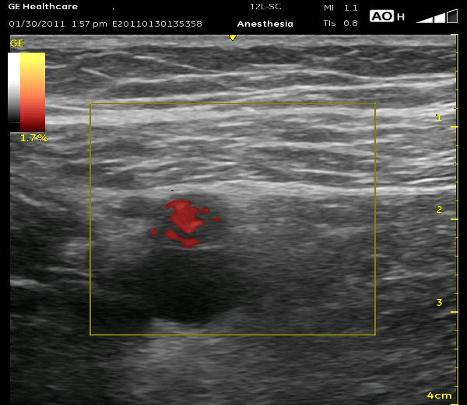

Here are a few technical points for this block. As I have mentioned in another section, take a moment first to pause then ‘bounce’ up and down to identify the Femoral Vein (adjucent to or below the Femoral Artery) or other vascular structures that may be collapsed. Color-flow may be helpful as well, especially the more distally you are. Note that in the ultrasound picture below, the subcutaneous tissue (when there is a lot of it) above the muscle can be mistaken for the muscle itself, and you will be looking too superficial for the artery. Try to notice the slight difference between the long and wavy lines within the fat and the straight and more uniform lines within the muscle. The Femoral Vein can be seen beneath the Femoral Artery here. Retrace with your probe to confirm structures (fall-off of the VM and appearance of the next ovoid shape) if it becomes confusing. When the local is injected, watch to see that if you crossed the Sartorius muscle, the local does not fill within the muscle itself. The local should swell the ‘collapsed triangular-shaped plane’ in which the artery and nerve reside. I don’t think it is an issue to try to determine whether or not you are within the Adductor Canal. I avoid the Sartorius more now, and I always stay out of the VM. This kind of anchoring is painful, causes more bleeding and VM contraction may significantly move the catheter tip.